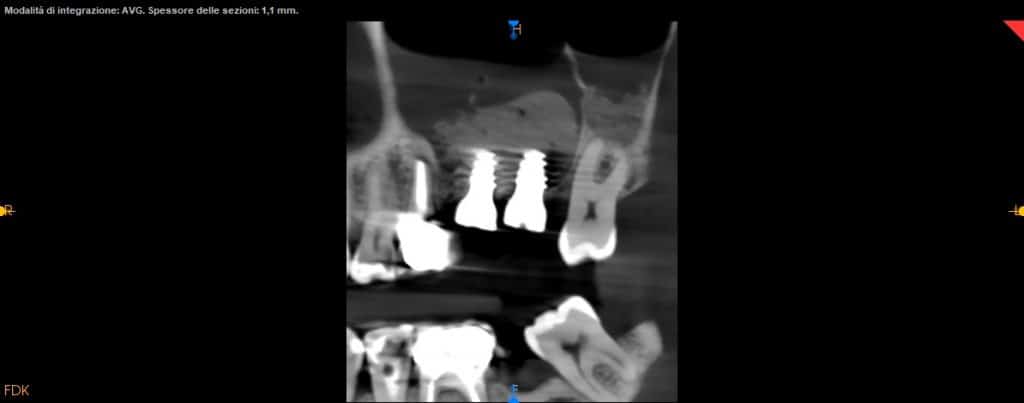

- CBCT helps us for the exact position of the window

- CBCT should guide the detachment of the sinus membrane

- Attention should be paid to any bone septa highlighted by the CT scan

CBCT

axial view

CBCT control